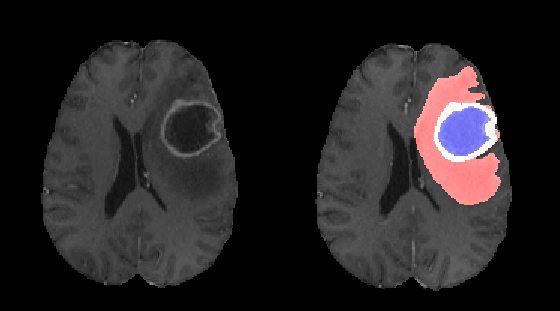

Brain gliomas can be well detected using magnetic resonance imaging. The whole tumor is visible in T2-FLAIR, the tumor core is visible in T2 and the enhancing tumor structures as well as the necrotic parts can be visualized using contrast enhanced T1 scans. An example is illustrated in figure 1.